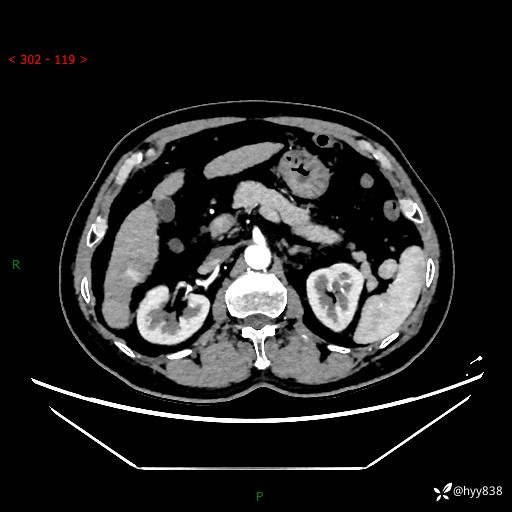

延迟期